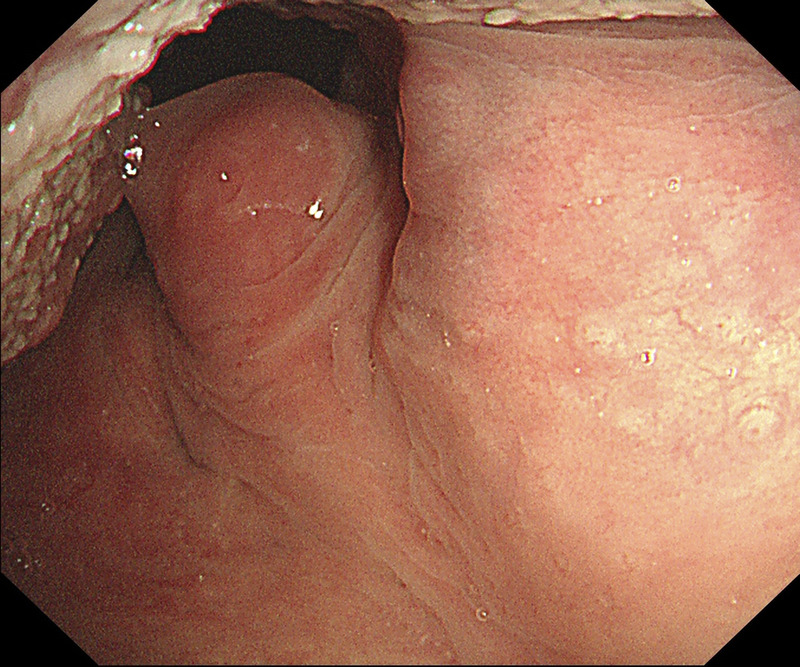

EUS-FNA to diagnose a submucosal oropharyngeal carcinoma.